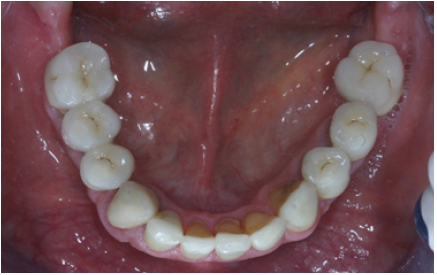

Figure 18: Final restorations occlusal view of the mandible.

Preparations for veneers, final result

In order to optimize final aesthetics the 5 mandibular anteriors were prepared for all ceramic restorations. Four all ceramic veneers (E-max Ivoclar Co, Liechtenstein) and an all ceramic crown (#42) completed the final restorations. A final occlusal splint was also fabricated chairside (prior to the final cementation of ceramic veneers) for the protection of final restoration and control of TMJ function (Figure 19,20). Minimal occlusal modifications of the splint were necessary after final cementation of mandibular anteriors. The final radiographic examination was kept as a record for future re-examinations (Figure 21). Finally, the patient was enrolled to a 3 months recall program. In each recall and maintenance visit, the periodontal tissues, the abutments and the stomatognathic system were thoroughly examined, preventive regimens were applied and patient compliance was assessed. Two years later, the excellent periodontal condition and performance of the restoration was registrated (Figure 22-24). The patient complied with proper oral hygiene, reduced smoking and adopted a regular use of the occlusal splint. Strict recall and maintenance visits were necessary for long term success of this full mouth rehabilitation. The patient stopped smoking immediately after 6 months and changed nutritional habits in order to eliminate secondary caries.